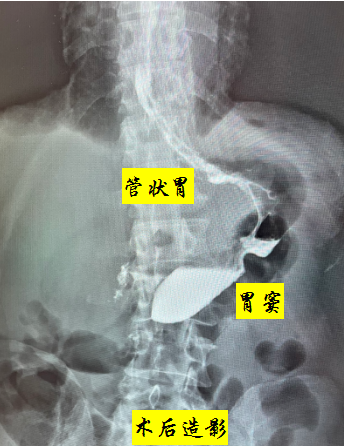

64岁王某,4月前在兰州某医院确诊为胃癌(cT2NxM0),因合并肺气肿、高血压3级、乙肝及脑出血病史,且长期口服抗凝药物,存在手术相对禁忌症,遂给予2周期SOX方案新辅助化疗,期间积极处理合并症。2周期化疗后行胃镜检查提示:贲门病变性质待查(化疗后改变)。病检提示:(贲门)高分化腺癌。CT检查提示:贲门小弯侧胃壁局部略增厚,浆膜面光整。该患者经术前新辅助治疗后病情进一步缓解,且病灶局限,无淋巴结及远处转移,治疗以手术首选,但考虑到患者年龄较大,合并症较多,在保证肿瘤R0切除的前提下为降低围手术期并发症,经与家属充分沟通各类术式的近远期疗效及并发症后最终决定行近端胃切除术。然而考虑到目前近端胃切除后不论是间质空肠、双通道吻合还是胃食管直接吻合,术后反流性食管炎等相关并发症发生率均较高,而Kamikawa吻合可减少反流性食管炎的发生率,并降低了吻合口瘘的风险,但是操作相对复杂,手术时间长,考虑到该患者基础疾病较多,可能不能耐受较长的手术时间。研究报道GIRAFFE重建操作相对简单,手术时间短且有很好的抗返流效果,消化病院区胃外科腹腔镜胃癌团队在聂蓬主任的带领下紧跟胃癌诊疗国际前沿,深入学习探讨,积极临床实践,在做好充分的术前准备的基础上,成功为该患者开展了腹腔镜下近端胃切除后食管胃GIRAFFE重建,手术效果良好。

聂蓬主任介绍,GIRAFFE重建具备以下特点:1.维持了正常生理通道,便于术后残胃及十二指肠的内镜检查;2.保留了远端胃,既可以用来储存食物,也因远端胃明显的收缩活动产生的机械碾磨,将食物颗粒与胃液搅拌混合,最后把食糜推进到十二指肠;3.保留部分位于胃体中部大弯侧距贲门5~7 cm的区域胃电起搏点,维持良好的术后胃排空能力;4.具有很好的抗返流效果,GIRAFFE重建首先通过重建胃底,阻挡一部分反流的残胃内容物,残胃内容物涌入人工胃底后造成局部压力增加,进而通过重建的His角对管状胃远端形成压迫,减少进入管状胃的残胃内容物,间置于食管及残胃之间的管状胃发挥抗反流缓冲带作用,缓冲冲向食管的胃内容物;5.游离的管状胃亦可充分解决吻合口的张力问题。所以,该重建方式操作简单,安全可行,效果好。